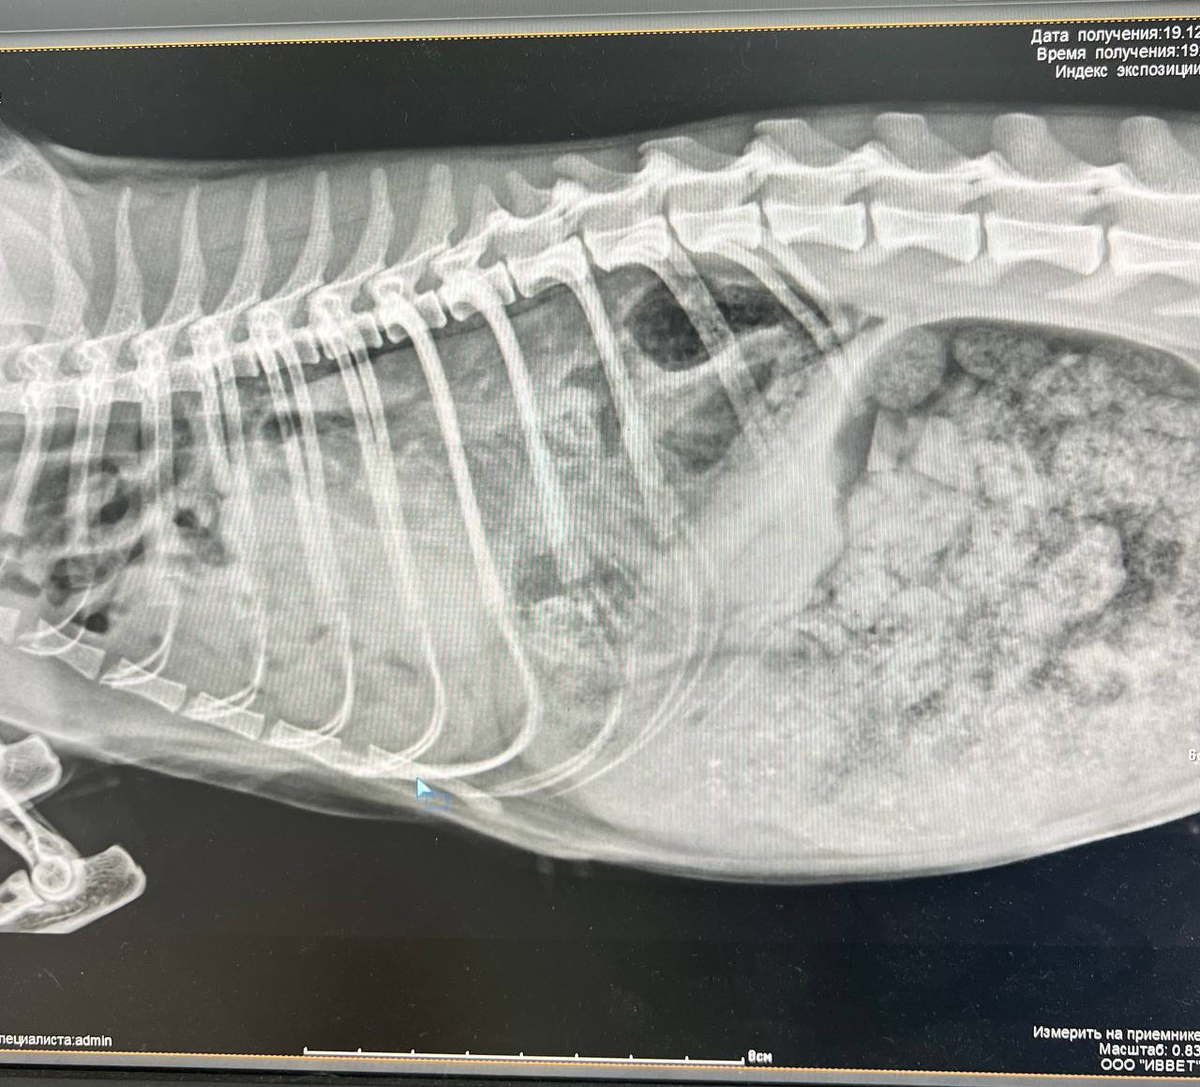

При рентген-обследовании была выявлена диафрагмальная грыжа😞 Это серьезная травма, угрожающая жизни. При такой травме внутренние органы брюшной полости через дефект в диафрагме частично выпадают в грудную полость, нарушая дыхание у животного. Что в конечном итоге приводит к смерти животного. Эту проблему необходимо

При рентген-обследовании была выявлена диафрагмальная грыжа😞 Это серьезная травма, угрожающая жизни. При такой травме внутренние органы брюшной полости через дефект в диафрагме частично выпадают в грудную полость, нарушая дыхание у животного. Что в конечном итоге приводит к смерти животного. Эту проблему необходимо решать срочно. Но у нас нет денег на операцию. Ее стоимость около 20 тысяч. Операция предварительно назначена на понедельник-вторник. Кот пока будет находится в стационаре на кислородо-терапии и обезболивании.